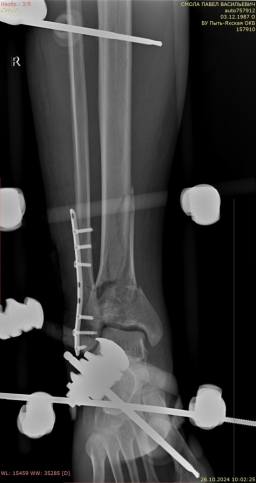

Через 27 дней после травмы был выполнен окончательный блокируемый остеосинтез правой большеберцовой кости интрамедуллярным стержнем с антибактериальным покрытием (рис. 9).

Рис. 9.